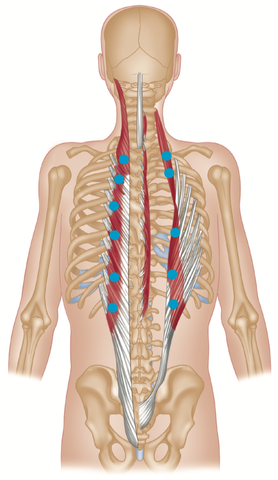

Con questo nome si identifica una sindrome dovuta ad un’errata postura nell’uso di apparecchi elettronici, che causa dolore e infiammazione a carico del collo, delle spalle, delle zone cervicale e toracica della colonna vertebrale, ipertrofia ed ipotrofia dei muscoli del collo, fino a modifica delle curve vertebrali, scompensi posturali e disfunzioni neurologiche.

La postura che, spesso, si assume nel guardare gli schermi di tablet, telefoni e computer porta la testa fuori dal suo asse naturale per molto tempo, andando a caricare le strutture con un peso fino a 5 volte maggiore del carico ordinario : la testa in posizione naturale pesa circa 5kg, inclinata di 60° arriva a pesarne 27.

Un carico di questo tipo, prolungato per molto tempo, può portare ad un eccessivo lavoro in contrazione ed estensione dei muscoli del collo, mentre tutto il corpo cerca di adattarsi per sostenere una visione frontale.

Localmente, tendono ad essere allungati ed indeboliti:

Questi muscoli, costituiti dai muscoli lungo del collo e lungo della testa, si trovano lungo la parte anteriore del rachide cervicale e aiutano a stabilizzare il collo. Quando si indeboliscono, i flessori cervicali profondi si allungano mentre il mento si inclina allontanandosi dal collo.

Questi sono muscoli estensori attaccati alla parte posteriore del rachide cervicale inferiore e alla colonna vertebrale toracica superiore. Svolgono un ruolo chiave nel ruotare e raddrizzare la colonna vertebrale. Quando i muscoli della spina dorsale si allungano e perdono forza, perdono la capacità di tenere dritti collo e schiena.

Trapezio medio e muscoli romboidi nella parte superiore della schiena portano le scapole all’indietro per mantenere le spalle ed il petto in una postura corretta. Trapezio e muscoli romboidi indeboliti permettono alle scapole di inclinarsi anteriormente, contribuendo ulteriormente a spalle curve e ad una postura della testa in avanti.

Localmente, tendono ad essere accorciati e contratti:

Queste quattro paia di piccoli muscoli, che collegano la parte bassa del cranio alla parte superiore delle cervicali, aiutano nella rotazione e nell’estensione della testa. Questi muscoli sono costantemente coinvolti nel mantenere la testa inclinata verso l’alto per guardare frontalmente.

Poiché i muscoli nella parte superiore della schiena tendono ad allungarsi perchè le spalle sono spostate in avanti, i muscoli pettorali possono accorciarsi e contrarsi. Potrebbero, per esempio, essere contratti i pettorali minori.

Questa coppia di muscoli si trova lungo la schiena e i lati del collo, viaggiando dalla colonna cervicale superiore fino alla scapola (scapola). La scapola levatrice svolge un ruolo chiave nel sollevare o elevare la scapola, oltre ad aiutare nei vari movimenti del collo. Se la scapola inizia a inclinarsi in avanti e a ruotare verso l’alto con spalle arrotondate, i muscoli scapole del levatore possono accorciarsi.